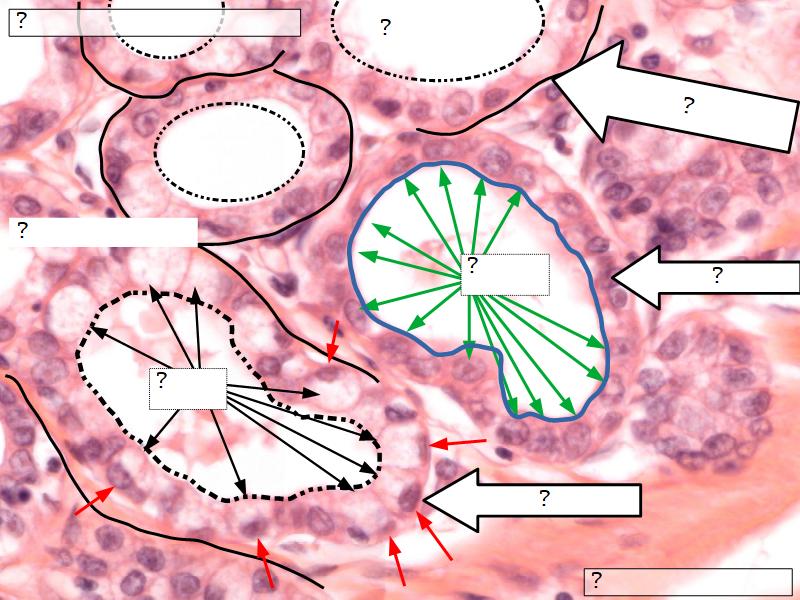

Active gland

- Much larger than resting phase

- Terminal ducts proliferate to form alveoli

- Alveoli

- Surrounded by incomplete myoepithelial cells

Alveolar cells

- Apocrine secretion

- Active state

- Resting state